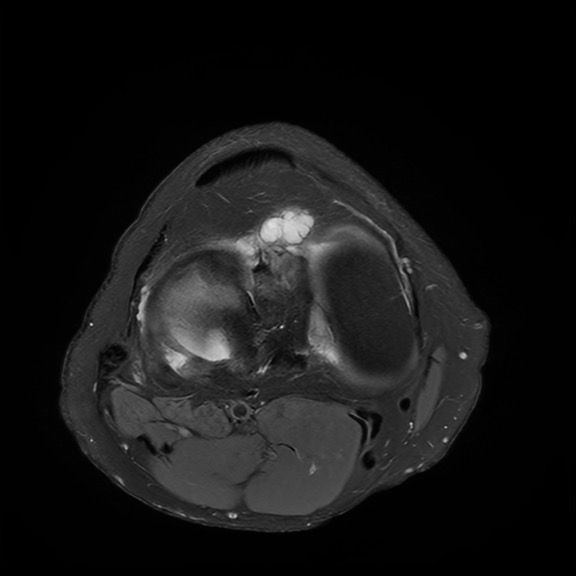

글개건하에 보이는 것은부종이나 혈종, 점액낭염일 수 있고 프롤로 주사 후 일시적인 변화일 가능성이 있어요 MRI에서 슬개건의 두께 변화나 고신호가 보이면 슬개건염 소견에 해당하고 정밀 판독 전까진 예단하기 어렵습니다!

첫번째 두번째 사진은 슬개건하부에 염증으로 보이며

잼액낭의 변성일수도 있겠습니다.

세번째 사진은 무릎 중심부에 십자인대에도 염증 반응을 보이고 있는 것 같습니다.

일반적으로 슬개건염(Patellar tendinitis)은 슬개골 아래쪽, 즉 슬개건 부위에 건의 부종, 신호강도 증가(염증), 미세 파열 등이 MRI에서 보이는 특징입니다. 특히 T2 강조 영상에서 슬개건 내 고신호(밝게 보이는 부분)가 나타나면 염증성 변화로 해석될 수 있습니다. 만약 이런 신호가 크지 않거나 경계가 뚜렷하지 않다면 경미한 슬개건염일 수 있으며, 보존적 치료(물리치료, 스트레칭, 소염제 등)로도 충분히 회복될 수 있죠

슬개건 하방(아래쪽)에 무언가가 있다는 표현은 몇 가지 가능성을 시사합니다. 대표적으로는 슬개하 지방체(호파 패드)의 염증이나 부종이 해당 부위에서 흔히 발견됩니다. 이는 점액낭염처럼 보일 수도 있고, 운동 후 반복적인 압박이나 마찰로 생기기도 해요. 혹은 점액낭(버사)이 부어있거나, 아주 드물게 결절성 병변, 낭종, 또는 혈종 등이 있을 수도 있습니다. 초음파나 MRI 판독 결과에서 "fluid collection(액체 고임)" 또는 "edema(부종)"이라고 나오면 비교적 경미한 문제일 가능성이 높습니다.